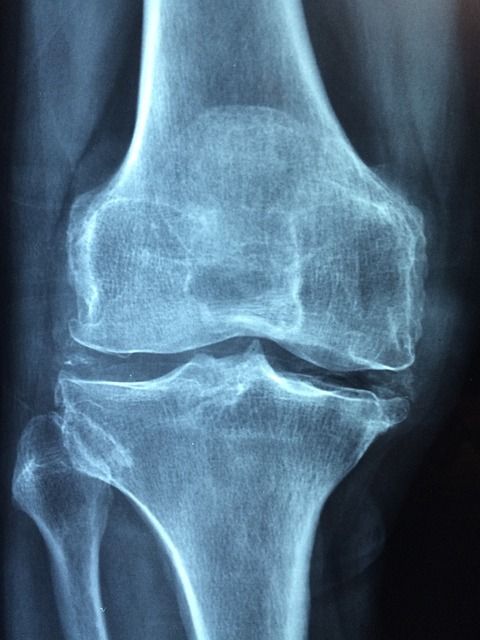

그 외에도 혈액 검사로 요산 농도를 측정하고, X선이나 초음파, CT 등의 영상 검사로 관절 손상과 통풍 결절을 확인할 수 있습니다. 급성 발작 시 혈중 요산 농도가 일시적으로 떨어질 수 있으니, 증상이 없을 때 검사를 반복하는 경우도 있습니다.